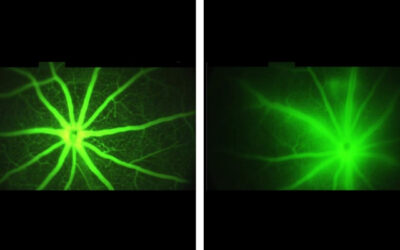

Ensayos de terapia génica para DMAE húmeda

Ensayos de terapia génica para DMAE húmeda Ensayos de terapia génica para la degeneración macular húmeda relacionada con la edad (DMAE). Después de una serie de ensayos fallidos, la esperanza se vislumbra en el horizonte para la viabilidad de la terapia génica para la...